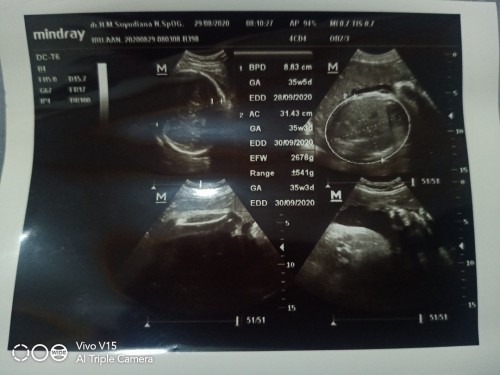

setauku ya bun usia kandungannya 35w3d perkiraan lahir kalau menurut usia kandungan 30-09-20 berat janin 2678gram

usia kehamilan 35w3d, hpl usg 30-9-2020, kisaran berat janin 2678 gram